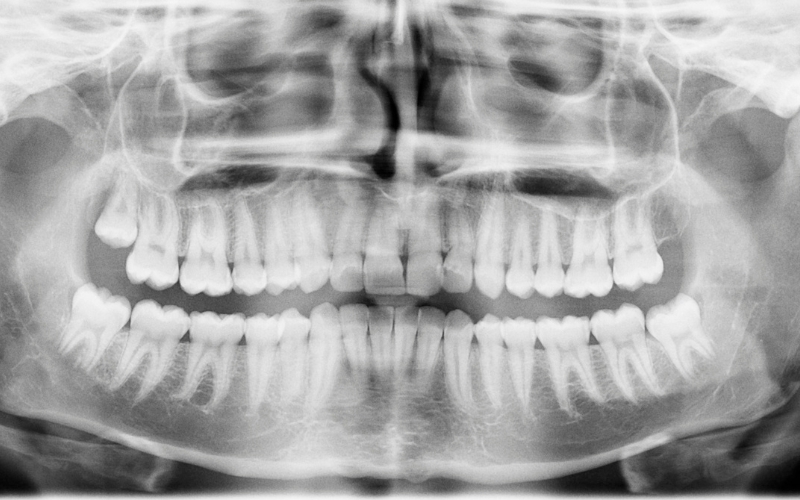

Sådan kan du effektivt hjælpe retsodontologerne i identifikationssager

Få et overblik over, hvordan du kan sikre de bedst mulige betingelser for retsodontologernes arbejde med at identificere afdøde personer med ukendt identitet.